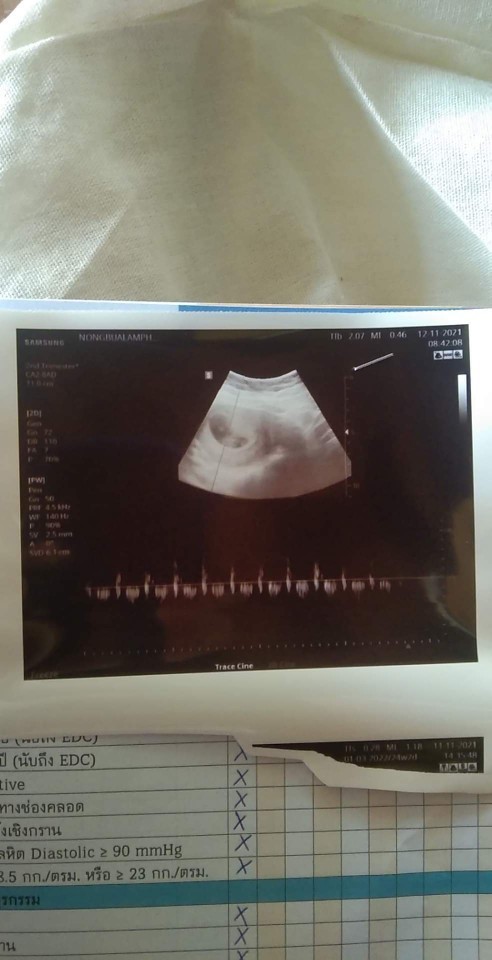

บ้านนี้7wกับ5dคะ

บ้านนี้7weekค่ะ

บ้านนี้ 7 w ค่ะ